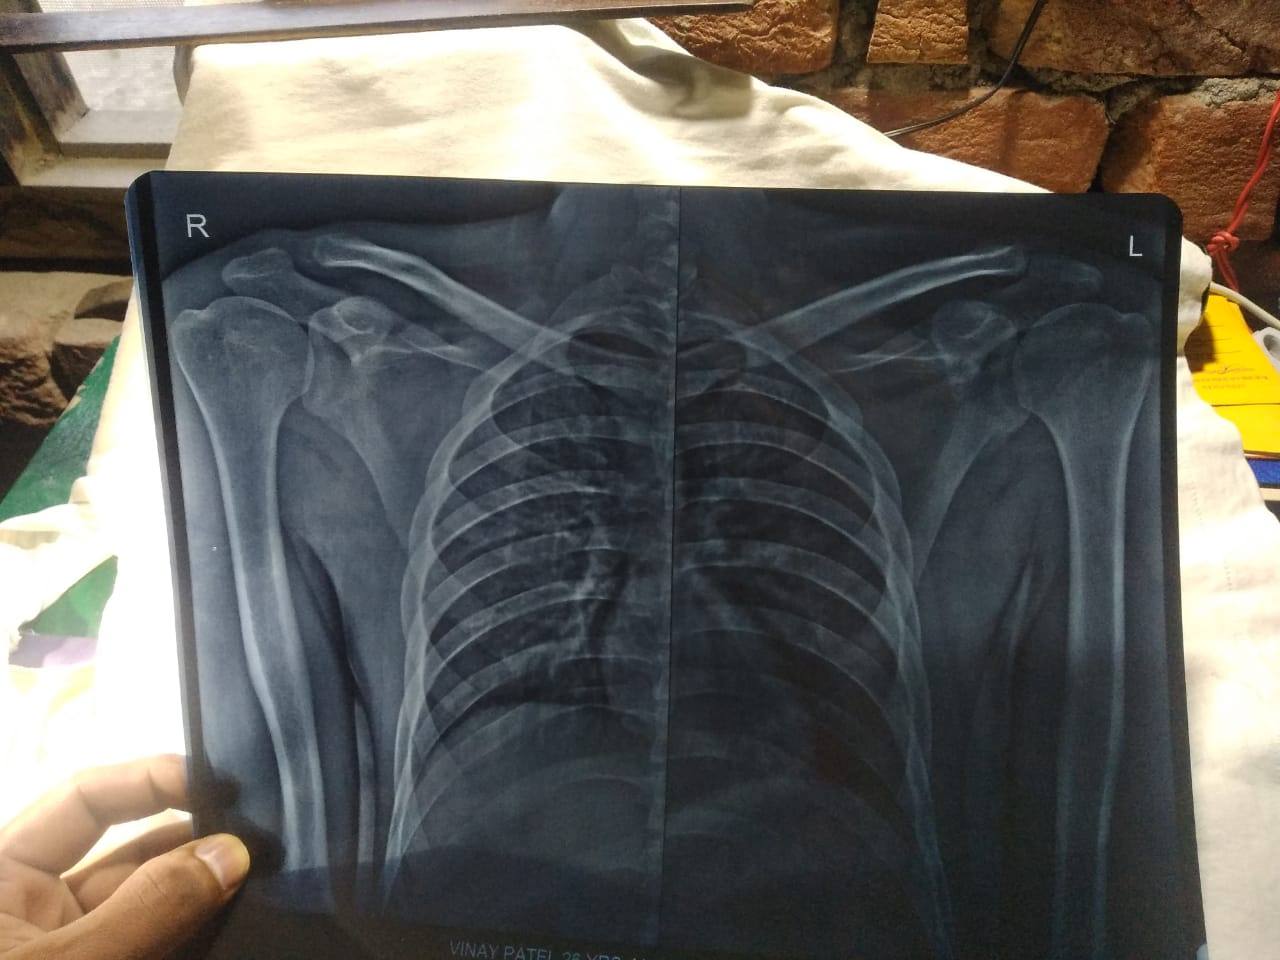

Sir mera right shoulder ak bike accident ke bad thoda upr ubhra hua dikhne lga hai mai UP gorakhpur se hu apne vha kai jagah dikha diya sab doctor log bol rhe hai ab jaisa hai accept kar lo , par mai chahta hu aap se ak bar mil ke dikhane ke bad mai accept kru sir us accident ke bad kamar me mujhe humesha dard rhta hai aur study krne me bhi dikkat hoti hai abhi 9 month ho gye hai accident ke,agr sambhav ho to jarur bulaye sir